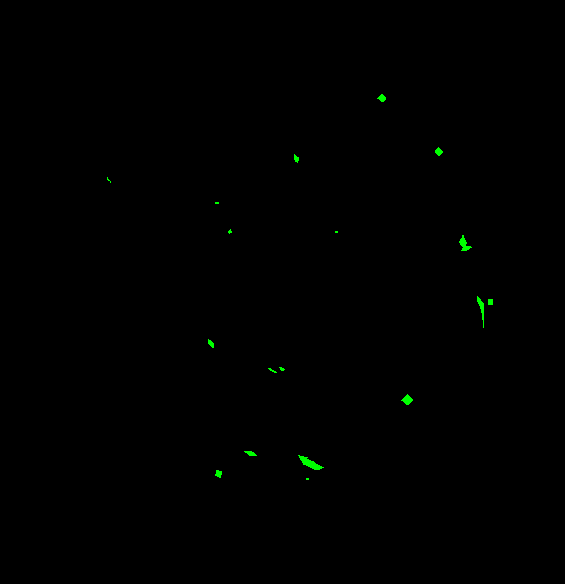

The visual differentiation between arteries and veins can be difficult in some cases, like small vessels with poor contrast and not clearly connected to a specific arterial or venular tree. These cases can be identified with certainty as vessels, but their classification into arteries and veins is uncertain, even for an expert. Additionally, it is common to find crossings between arteries and veins in the retina. Thus, although for these positions either the artery or the vein is above the other, these pixels can be regarded as simultaneously belonging to both types of vessels. This allows to account for continuous arterial and venular trees regardless of crossings below the other one. The identification of these two special situations (uncertain vessels, and vessel crossings) is common in manually annotated retinal vessel classification datasets [38, 42, 43, 44]. Figure 1 shows an example of a ground truth image from the RITE dataset labelled this way, along with its decomposition into arteries, veins, crossings and uncertain vessels.

In addition to this feature, it is also relevant to note that, in this case, the “uncertain” class does not include the vessel crossings, unlike the “uncertain or crossing” class defined in the traditional approach. Instead, in this approach, the vessel crossings are encoded as the superposition of the artery and vein segmentation maps, which should be both indicating positive class for these pixels. In order to do that, the ground truth for each class should be adapted to the output of the network and these restrictions. This can be achieved by considering the vessel crossing regions as positives in both artery and vein segmentation maps, and combining these two maps with the uncertain vessel regions to obtain the vascular tree segmentation map. An example of such an adapted ground truth is shown in Figure 3. Additionally, this setting allows to detect vessel crossings through the intersection (product) of the predicted arteries and veins segmentation masks.

Also, an example of a retinography and its corresponding vasculature segmentation and A/V classification ground truths is depicted in Figure 6.

In order to train the networks following the traditional and MS approaches, the ground truth images from the RITE dataset are adapted, in each case, to the output of the network. In the traditional approach, each pixel of the ground truth is assigned to either background, artery, vein or “uncertain or crossing” class, which comprises both uncertain vessels and crossings. The resulting ground truth is a grayscale image in which each pixel has a numeric label of the class to which it belongs. On the other hand, in the MS approach, each pixel is assigned to any number of the following classes: artery, vein and vessel. In this case, crossings belong to the three classes, and uncertain vessels belong only to the “vessel” class. Background pixels are not assigned to any class. The resulting ground truth is an RGB image in which each channel contains a manual segmentation mask of one of the aforementioned structures. An example of a RITE ground truth adapted to both the traditional and the MS approaches can be found in Figure 7.

As commented above, we include an extra evaluation for the proposed approach. This evaluation is focused on assessing the performance of the approach in the vessels crossings localization task. For this purpose, it is necessary, first of all, to define how the output of the network and the ground truth are translated to a set of coordinates representing the vessel crossings. In this process, the first step is to obtain the ground truth and the predicted segmentation masks of the crossings. This is achieved by performing an element-wise product of the artery and vein channels, as the vessel crossings belong to both classes. Then, for the prediction, we use an intensity threshold followed by a small dilation to merge very close regions. Once the prediction is converted to binary and dilated, we perform a connected-component analysis (CCA) and compute the centroids of the detected regions for both the prediction and the ground truth. The coordinates of the detected centroids are the ones used in the evaluation. As gold standard, as it is done in [64], we consider a predicted crossing a True Positive when it is within a certain distance of a crossing from the ground truth. Otherwise, it is considered a False Positive. Also, a crossing can be predicted only once. Thus, in each case, only the closest prediction within the distance is considered as a True Positive. The crossings that are not located within this distance of any ground truth crossing are considered False Negatives. This analysis is performed for a representative distance of 10 pixels (). Finally, in order to build the PR curve, we use these measurements to compute the Precision and Recall metrics for a moving threshold over the entire test set.